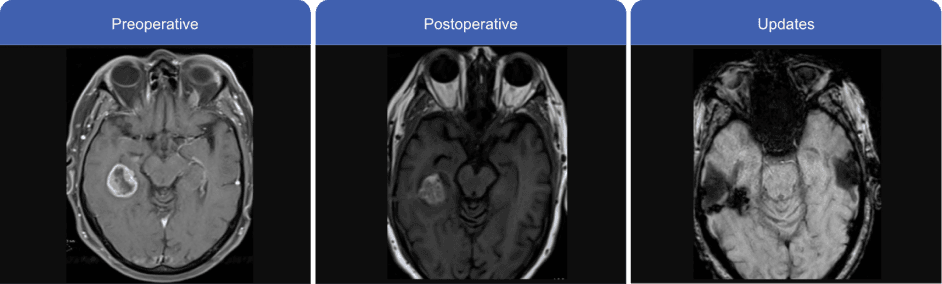

Patient's MRI

Case information used with permission from Kellie Kopp, RN, BSN, OCN.